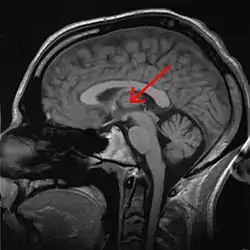

Таламус або талямус (лат. thalamus dorsalis, від грец. θάλαμος — «кімната», «шлюбне ліжко») — ділянка сірої речовини у верхній частині проміжного мозку хордових тварин. Таламус є симетричною, розміщеною обабіч міжпівкульної серединної лінії, структурою, складеної з двох однакових половинок. Він розміщений між структурами великого мозку, зокрема корою, та структурами середнього мозку. Серединна поверхня обох половинок таламуса є водночас верхньою боковою стінкою третього шлуночка головного мозку.

![]() Таламус на зображенні з МРТ | |